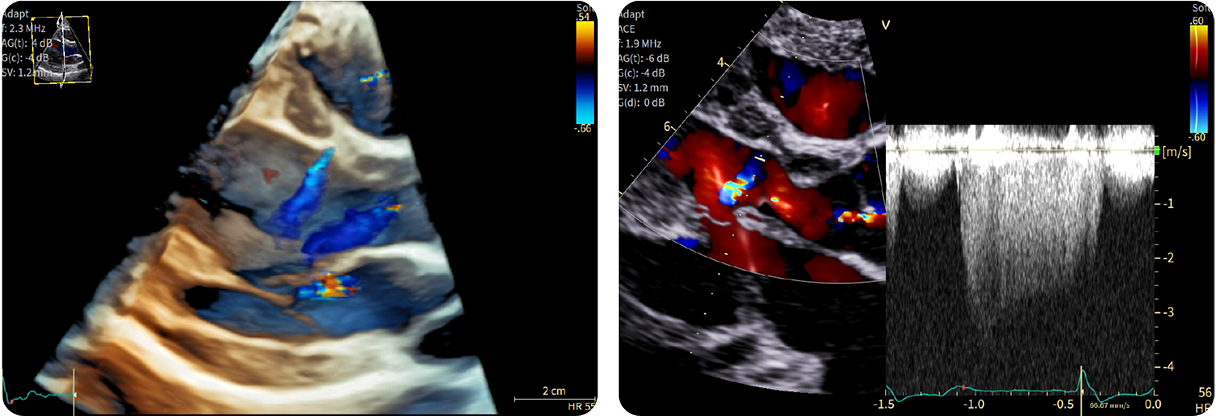

Fifty shades of grey

Caso condiviso da Marcello De Santis